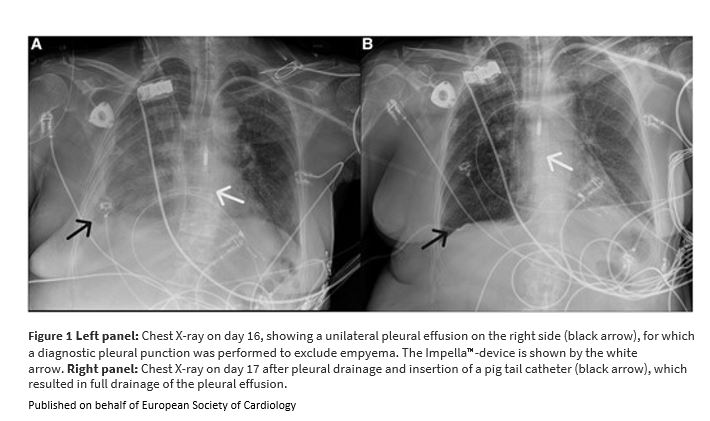

#cathlabhack for #impella placement. Maybe it is common knowledge but I have just recently heard about it from Dr. Spangenberg and would like to share it: after wire pullback from LV into ao arch->advance the wire into AV sinus-> bingo -> easy positioning of the cannula @BotPci